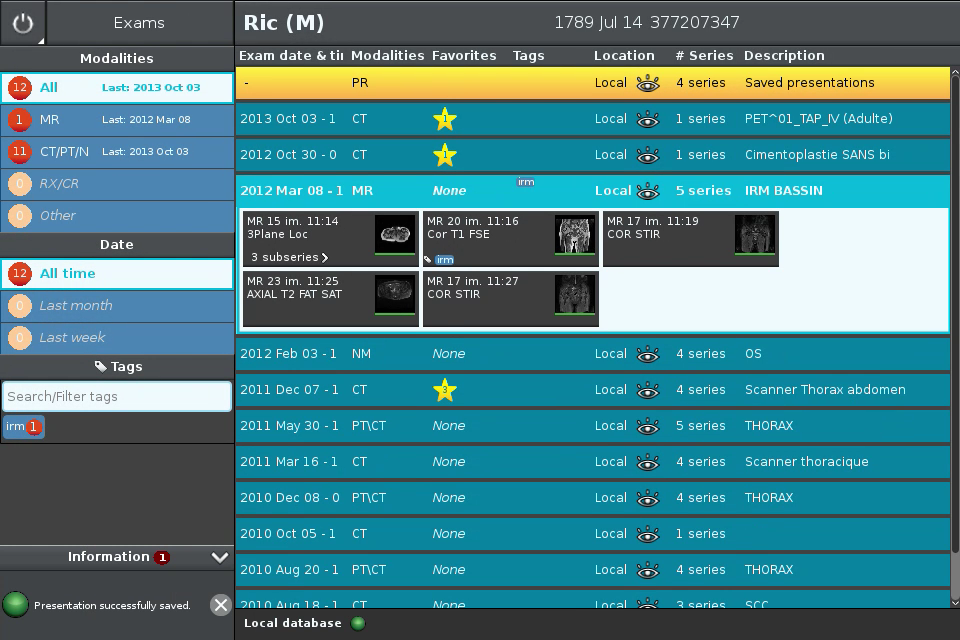

Anywhere Streaming is a DICOM visualization client that connects to Anywhere Server. It provide standard medical image navigation tools surch as : slicing, windowing, MPR, 3D VR, MIP, oblique ...

All standard medical image modalities are supported : MR, RX, CT, PET, NM, MG, US ...

Screenshots